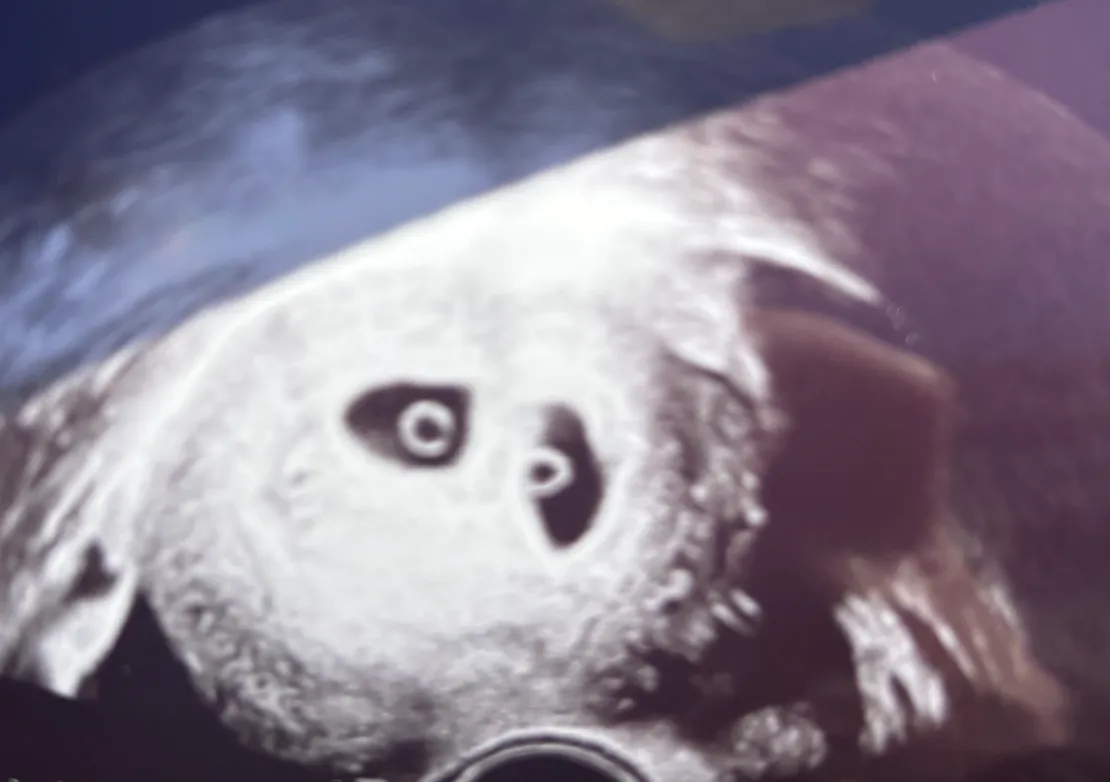

쌍둥이 임신 다자녀 아빠가 될 예정이다. 여기서 내가 말하는 다자녀는 저출산 기조로 최근에 바뀐 2명 기준의 다자녀가 아니라 3명 기준의 다자녀다. 둘째가 쌍둥이란다. 전혀 예상하지 못했고 아직도 실감이 나지 않는다. 이번 인생의 난이도 확 올라가버렸다. 인생에서 아이가 생긴다는 것은 큰 변화며 전환점이다. 임신, 출산, 육아에 필요한 리소스, 고민, 스트레스는 그동안 우리가 겪어왔던 문제, 고민, 스트레스에 비교 대상이 되기 힘들 것이다. 그럼에도 불구하고 아이가 생긴다는 것은 너무나도 크나 큰 행복이며 축복이다. 조용할 틈 없이 왁자지껄한 미래 우리 가족의 알콩달콩 모습이 너무 기대된다. 독서모임 2024년 5월 1회차로 시작한 독서모임이 2025년 12월로 32회차가 되었다. 책을 더 많이 읽기 위한 환경에 나를 던져놓고 싶다는 생각에 무턱대고 후다닥 만들게 되었고, 소규모지만 지속되고 있다. 2025년에 실제 오프라인 모임이 진행된 회차는 7회였다. 독서모임에 많이 가본 것은 아니지만, 직접 경험해본 독서모임과 인터넷에 올라오는 후기들을 보면 지속되는 것이 생각보다 쉽지 않다. 특히 실질적인 도움을 주는 자격증, 재테크, 기술 관련 독서 모임이 아니라면 더더욱말이다. 내가 운영하고 있는 모임은 철저하게, 실질적인 도움을 주는 모임과는 거리가 멀다. 지금까지 진행한 책 몇 가지만 소개하자면 <이반 일리치의 죽음>, <반쪼가리 자작>, <소년이 온다>, <넥서스> 등이 있다. 이런 책들은 다 읽는다고 해서 당장 우리를 밥 먹여주지 않을 가능성이 높다. 처음 독서모임 운영을 위해 정리했던 책 선정 규칙은 아래와 같다. 우리가 책을 독서모임에서만 읽지는 않을테니, 본업을 위해 필요하거나 직접적인 정보나 지식을 얻을 수 있는 책은 각자 알아서 보는 게 좋겠다고 판단했다. 오히려 인생을 장기적인 관점으로 바라봤을 때 아래 기준에 맞는 책들을 우리가 읽을 기회는 매우 적으나 큰 가치가 있다고 생각했다. 인생, 삶에 대해 생각해볼 수 있는 책 지적인 성장을 기대할 수 있는 책